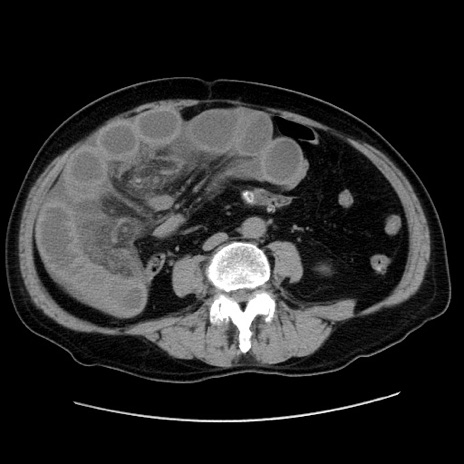

症例30(横断像)

【症例】80歳代男性

【主訴】臍周囲痛

【現病歴】約6時間前から臍下部痛が出現。次第に腹部膨隆・背部痛も生じてきたため来院。背部痛の場所は変化しない。

【身体所見】意識清明、BT 36.3℃、BP  131/87mmHg、P 87bpm、SpO2 100%(RA)、臍周囲自発痛・圧痛あり、反跳痛なし、自発痛部位に一致して板状硬あり、腹部膨隆、腸雑音減弱、CVA tenderness両側陰性。

【データ】WBC 19600、CRP 0.33